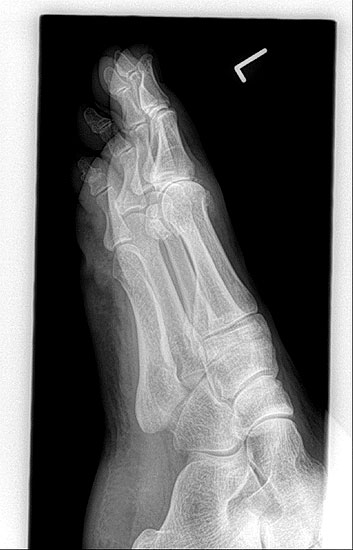

• Röntgenaufnahmen des Vorfußes (unter Belastung) im dorsoplantaren und seitlichen Strahlengang (Abb. 1a+b)

• Beurteilung des Erkankungsstadiums anhand der typischen Arthrosekriterien (Einteilung nach Regnauld) 2

• Beurteilung des Intermetatarsal-Winkels (IMA), des Hallux valgus-Winkels (HVA), mögliche Korrektur der des IMA von 6° durch alleinige Arthrodese, darüber hinaus evtl. zusätzliche MT-I-Korrektur notwendig 101112

• Beurteilung des Metatarsale-Index und der Zehenlänge DI und II, insbesondere nach Voroperationen hinsichtlich einer evtl. notwendigen Verlängerung des ersten Strahls durch Knochenspaninterposition